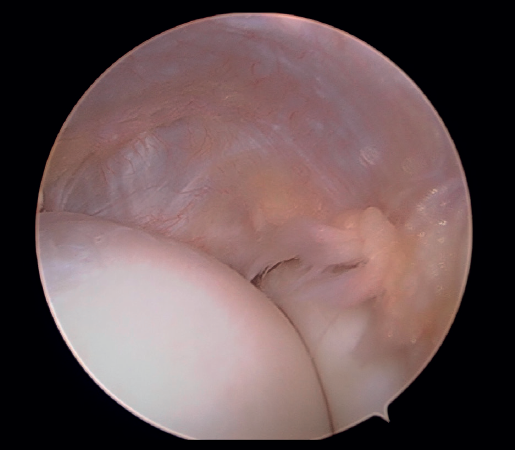

A continuación, se explora el compartimento anterior del codo en busca de sinovitis, lesiones condrales, cuerpos libres, plicas sinoviales o cualquier otra lesión, y se procede a su tratamiento mediante sinovectomía, desbridamiento, extracción o exéresis, respectivamente (Figura 6).

Posteriormente, se realiza la capsulotomía parcial lateral con sinoviotomo o vaporizador, hasta conseguir apreciar el ECRB (Figura 7). Una vez que se consigue su visualización, mediante el sinoviotomo y el vaporizador, se procede a la tenotomía de la inserción del ECRB en el epicóndilo, así como del tejido degenerativo tendinoso asociado (Figura 8). La liberación del tendón del ECRB debe limitarse a una zona anterior al eje central de la cabeza radial con el codo a 90°, para preservar la integridad del ligamento colateral lateral.

Figura 6. Compartimento anterior del codo, se aprecia la cabeza del radio y el cóndilo humeral junto con la cápsula articular lateral (paciente en decúbito lateral, codo derecho, visión desde el portal medial).

Figura 7. Tendón extensor carpi radialis brevis tras capsulotomía lateral (paciente en decúbito lateral, codo derecho, visión desde el portal medial).